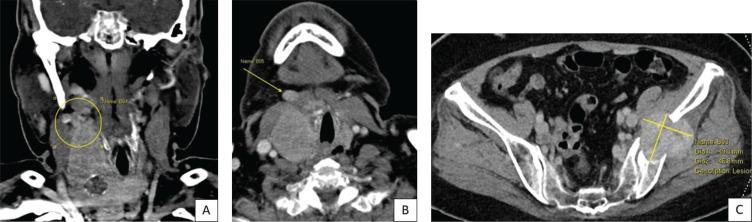

我们报告了一例67岁女性罕见的同步性乳头状甲状腺癌(PTC)和滤泡状甲状腺癌(FTC)的侵袭性病例,该患者最初因格雷夫斯病出现甲状腺毒症。她被发现有两个甲状腺结节,伴有广泛的心脏内肿瘤血栓、有症状的左骨盆骨转移伴病理性骨折、肺转移和纵隔淋巴结转移。进一步检查提示诊断为同步性乳头状和转移性滤泡状甲状腺癌。建议采用根治性手术,随后进行辅助性放射性碘消融治疗,但患者拒绝了所有形式的癌症特异性治疗,仅选择姑息性治疗方法。我们讨论了诊断同步性甲状腺恶性肿瘤时的诊断要点——在本病例中,PTC的明显特征以及由于侵袭性和转移性滤泡病变导致FTC的高可能性。该病例强调了美国放射学会甲状腺影像报告和数据系统(ACR TI-RADS)的潜在局限性,特别是某些提示恶性的超声特征可能未被充分捕捉。值得注意的是,本病例中分化型甲状腺癌的侵袭性表现可能与格雷夫斯病的并存有关,这表明在评估此类患者的潜在甲状腺恶性肿瘤时需要提高警惕。